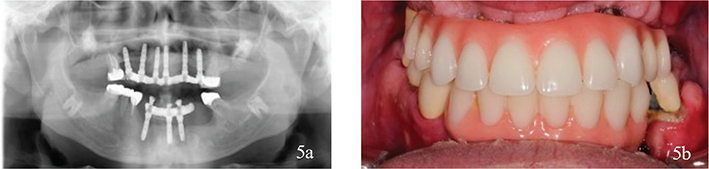

Figure 3

Interim prosthetics after removal of dental implants. A removable denture retained by fixed dental prosthesis on the molars in the maxillae and an interim acrylic prosthesis retained by teeth and the temporarily preserved implant in the mandible.